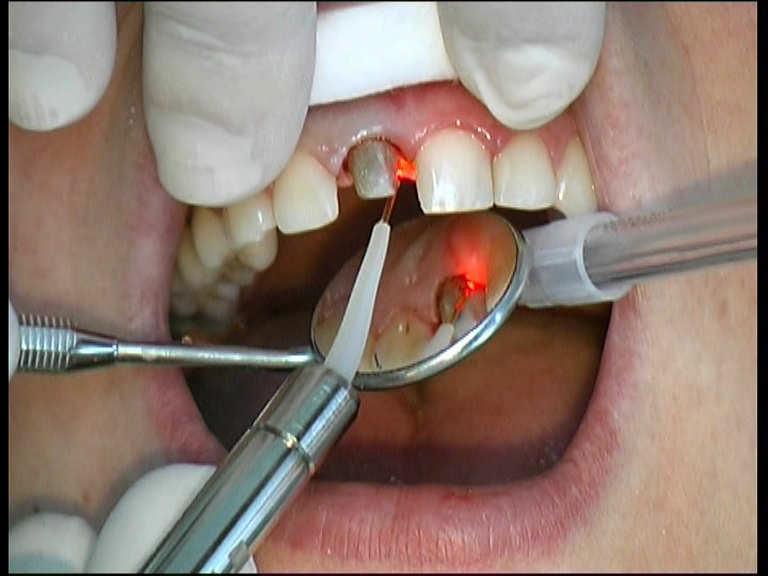

Prof. Alfred Resch

Laser Setting

Diode Laser 810nm

Power: 1,5 Watt, CW

Fibre 400 micron

Gingivectomy

Pre prosthetic